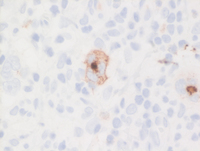

CD30 and CD15 in CHL

All classical Hodgkin lymphoma cells express uniform CD30 with prominent Golgi accentuation in many cells. Staining is typically cytoplasmic as well as membranous. Targeted therapy again CD30 (brentuximab) is available currently in the relapsed setting for cHL.

CD15 on the other hand, is positive in the Hodgkin cells and expression is often weak and focal with somewhat granular staining. Normally, numerous background neutrophils in the strong CD15 while background monocytes express moderate CD15 and serve as internal controls.